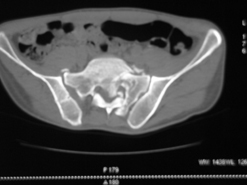

Диагноз : Сочетанная травма. ЗЧМТ. Перелом свода черепа. Ушиб головного мозга.Разрыв лонного и крестцово-подвздошного сочленений с нарушением целостности тазового кольца, с массивной забрюшинной гематомой и пропотеванием в брюшную полость. Перелом 10 ребра справа, осложненный гемопневмотораксом справа, правосторонней пневмонией на фоне ушиба правого легкого. Шок 3-4 ст. Больной поступил в отделение 07.03.2005г. в 16.00 в экстренном порядке через 30 минут после автодорожной травмы.Доставлен КСП. При поступлении состояние больного крайне тяжелое, явления травматического шока, А/Д-80/60 мм.рт. ст. ЧСС-120.В экстренном порядке поднят в операционную, интубирован, совместно с диагностическими мероприятиями лечение шока.При осмотре выявлены перелом 10 ребра справа, разрыв лонного и правого крестцово-подвздошного сочленений. Имеется линейный перелом теменной и височной костей слева с переходом на основание. Диагностическая лапароскопия 07.03.2005г. в 16.30-массивная забрюшинная гематома малого таза.Оставлена контрольная, дренажная трубка.Учитывая кровь в моче произведена цистография - данных за разрыв мочевого пузыря не найдено. Больной переведен в реанимационное отделение.За 08.03.2005г. из брюшной полости выделилось до 1500,0 мл, крови, часть крови реинфузирована. 08.03. в 06.30 наложен торокоцентез справа,удалено 100,0 мл. крови и 200,0 мл. воздуха .. Учитывая продолжающеееся кровотечение в брюшную полость из перелома костей таза, для исключения возможного разрыва внутренних органов 09.03.2005г. произведена Видеолапароскопия., на которой повреждения органов брюшной полости не выявлено.Одновременно произведен шов лонного сочленения проволокой и винтами, с одномоментным наложением стержневого аппарата на кости таза, с целью уменьшения кровотечения из разрывов тазовых сочленений, дренирование гематом. В последующем состояние больного оставалось тяжелым. 10.03.наложена нижняя трахеостома.Далее неоднократно производилась лечебно-диагностическая ФБС.С 10.03 выявлена правосторонняя плевропневмония. КТ головного мозга от 10.03-субарахноидальноекровоизлияние.Срединные структуры не смещены. КТ-контроль от 15.03-открытая моновентрикулярная гидроцефалия4 желудочка. Полисинусит. Постепенно состояние больного медленно прогрессировало к улучшению.С 24.03 переведен на самостоятельное дыхание, а 09.03 переведен в травматологическое отделение.Аппарат стержневой снят из-за перелома стержня (раскрутил больной самостоятельно).После госпитализации в наше отделение проведено дополнительное обследование Рентгекнография, КТ.Хотелось бы услышать Ваше мнение о дальнейшей тактике.-- С уважением, Leonid

Углядел билатеральное повреждение таза. Имеется вертикальная нестабильность со стороны перелома боковой массы крестца, ротационная с контрлатеральной стороны - чрезподвздошный разрыв кп сочленения. Разрыв лона, запирательные отверстия вроде целы.

DS. на сегодняшний день: Вертикальная двусторонняя нестабильная деформация таза, неправильно срастающийся перелом боковой массы крестца слева, срастающийся перелом крыла правой подвздошной кости, застарелый частичный разрыв правого кп сочленения, застарелый разрыв лонного сочленения.

План жизни - оперативное лечение. ЧКО таза (кольцевая опора), последовательная фиксация задних отделов с низведением перелома крестца, синтез лона пластинами, илиосакральное блокирование.